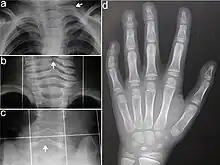

Typisch für das KBG-Syndrom sind faziale Dysmorphien (Gesichtsdysmorphien) und große obere mittlere Schneidezähne. Dazu kommen Anomalien des Skeletts, vor allem costovertebral, das heißt an den Rippenwirbeln, und eine verzögerte körperliche Entwicklung. Letztere führt zu Minderwuchs. Bei der Mehrzahl der Patienten finden sich außerdem EEG-Anomalien (mit oder ohne Krampfanfällen) und ein abnormer Haaransatz. Deutlich seltener sind kutane Syndaktylie, kurzer Hals mit Pterygium, Kryptorchismus („Bauchhoden“), Schwerhörigkeit, Schielen, Gaumendefekt und angeborene Herzfehler.[2]

Die Diagnosestellung erfolgt im Wesentlichen aufgrund der Symptome, da noch kein Gentest für das KBG-Syndrom verfügbar ist. Dabei orientiert man sich an vier wesentlichen Merkmalen des KBG-Syndroms: faziale Dysmorphie, Makrodentie der oberen mittleren Schneidezähne, skelettale Anomalien (vor allem costovertebral) und verzögerte Entwicklung. Im Alter von sieben bis acht Jahren lässt sich mit der Ausbildung der vorderen Schneidezähne über die Makrodentie die Diagnose sicherer erstellen.[2]